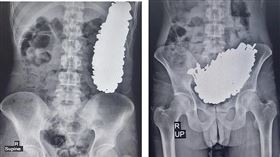

「鋼鐵人」是你?男吞452件螺絲塞滿胃

伊朗的醫學團隊在最新一期《醫學案例報告雜誌》(Jou...